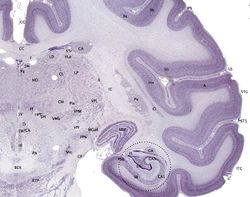

Brainmaps-macaque-hippocampus.jpg

القشرة المخية هي الطبقة الخارجية

تظهر باللون البنفسجي الداكن.

القشرة المخية إنگليزية: Cerebral cortex هي الطبقة السطحية من نصف كرة المخ لدى الثديات. والقشرة المخية لدى الأنسان تتكون من المادة الرمادية والتي يتألف معضمها من العصبونات الهرمية المرتبة في 6 طبقات فيما يعرف القشرة الجديدة. وهذا الترتيب هو ما يجعل مخ الأنسان معقد وقادر على الفهم والاستيعاب. كما يتيح هذا الترتيب إلى تقسيم المهام المختلفة إلى مختلف مناطق القشرة والتي سيتم ذكرها لاحقاً. كما أن القشرة المخية تتكون من الأخاديد والتلافيف التي تساعد على زيادة مساحة القشرة بشكل كبير (ثلثي القشرة تقع في الأخاديد). كما تستعمل الأخاديد - تشريحياً - في تقسيم المخ إلى مناطق وظيفية، بحيث تكون كل منطقة مسؤولة عن وظيفة محددة مما يزيد التخصيص والدقة في عمل الدماغ البشري. على الرغم من كمية المهام التي تؤديها القشرة فسماكتها تتراوح بين ٢-4 مم.